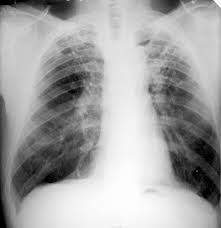

• Tuberculosis (TB). Nearly a third of the Indonesian people have been infected with TB. However, only 10% who manifest a disease. Most infections are found in the lung, also can attack other networks, highly contagious, spread through the air. Can live in moist air and not exposed to direct sunlight for a long time. Medication can work well, but must be lived in a long time (at least 6 months).